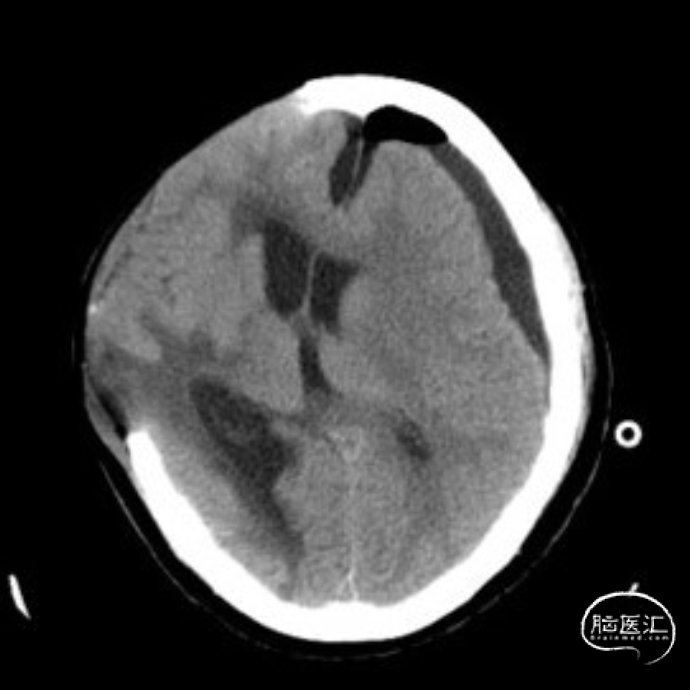

术后因为左侧硬膜下引流管欠通畅,患者逐渐出现意识障碍,复查头颅CT:左侧硬膜下积液增加,中线右偏。积极疏通引流管后患者意识障碍明显好转,复查头颅CT提示:硬膜下积液减少,中线回归明显。

第一次实验:开放腰大池引流管,关闭左侧硬膜下引流管,操作后患者意识逐渐变差复查头颅CT:左侧硬膜下积液开始增多。实验暂停,重新开放硬膜下引流管。

重新开放左侧硬膜下引流管,同时保持腰大池引流管通畅,患者意识恢复至清醒状态,复查头颅CT:硬膜下积液明显减少,中线回归,颅内压力明显降低。

第二次实验再次关闭左侧硬膜下引流,保持腰大池引流开放,患者意识变差,再次转入嗜睡,复查头颅CT提示左侧硬膜下积液增多。

再次开放左侧硬膜下引流后患者意识好转,第三次实验保持左侧硬膜下引流通畅,关闭腰大池引流,操作后患者病情稳定,复查头颅CT提示硬膜下积液减少,中线基本恢复。